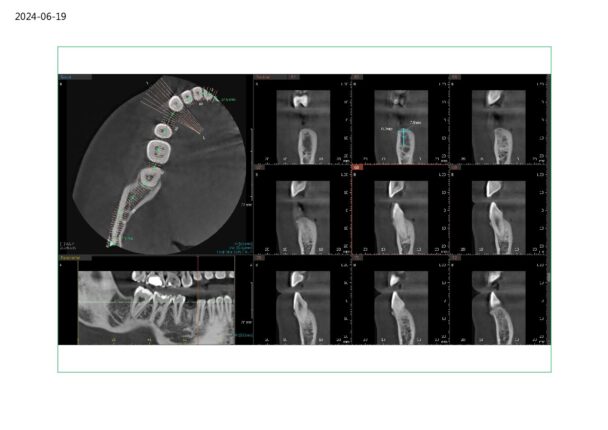

I have this implant case for tooth #28. I am worried about the anterior loop of the IAN here. It looks like it terminates at slice 62 and 63 but then I have a circular radiolucent area in slice 65. Do you think this is still the mental? If so I have about 10mm from the crest of the ridge. Do you think I’d be safe with an 8 mm implant here?

Just looking at what you provided it looks like there is sufficient room for an 8mm implant and that other slice I believe around 65 just looks like a void around the bone that looks similar to the pano version of the cbct and doesn’t present in other slices, nerve appears to be below that area.

Here are some screenshots of the CT for the case I am planning. Should I be concerned about the circular radiolucent area below 22 on page 2? When I traced it back I only saw it in a few segments. I remember Ivan saying there could be anterior branches of the IAN or vasculature in this region.